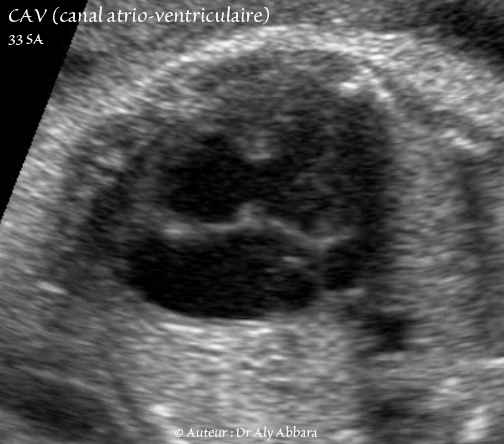

Canal atrio-ventriculaire complet - CAV - 33 SA - Vidéo et image animée échocardiographiques - القناة الأذينية البطينية - GIF animée

• Vidéo et image animée échographiques cardiaques montrant la présence de :

• un canal atrio-ventriculaire (CAV) complet.

• une valve atrio-ventriculaire (VAV) commune à une ouverture diastolique satisfaisante vers deux ventricules équilibrés (ventricule gauche "VG" et ventricule droit "VD" séparés pareillement par le septum interventriculaire "SIV" musculaire incomplet).

• une communication inter-auriculaire (CIA) de type ostium primum large aboutissant à la constitution d'une oreillette unique ou quasi unique (petit septum secundum "SS" au dôme de l'oreillette commune).

• la valve de Vieussens (V V) battant dans le secteur gauche de l'oreillette unique.

• une communication interventriculaire (CIV) très large ; il s'agit d'une communication de type de CIV d'admission.

• On observe également sur cette image la plaque modératrice (PM) battant dans le ventricule droit.

• L'aorte descendante (AO).

• Fœtus âgé de 33 SA trisomique 21.